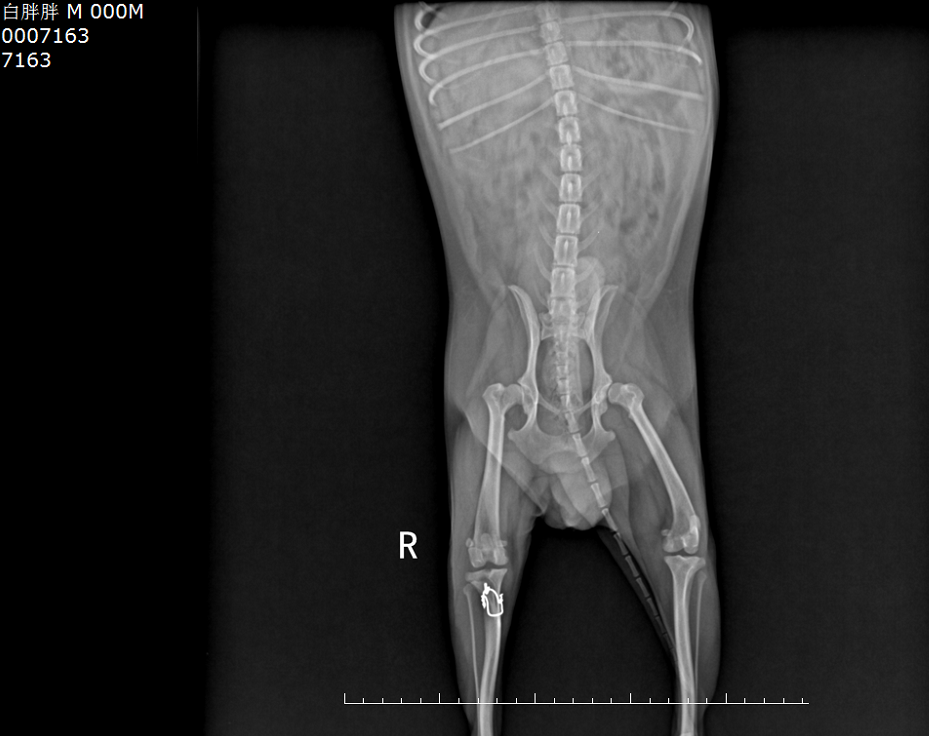

网上有一案例,一只髋关节切除术后狗狗食欲增加,运动量下降,体重迅速增长,并逐渐出现轻度跛行,运动不耐受的情况。

术后体重增加至5.5kg

@图源网络